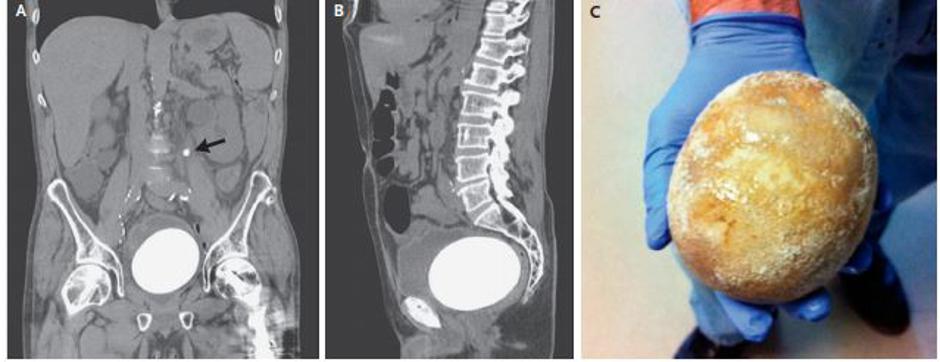

Možakar iz Kalifornije se je pritoževal zaradi hudih bolečin v spodnjem delu trebuha in težav pri uriniranju. Sledil je ultrazovk trebuha in zdravniki so imeli kaj videti.

Med medenico in trebuhom so namreč ugledali ogromen kamen, v velikosti grenivke, ki se je nesrečnežu naredil v mehurju. Zanimivo, da so Američanu pred desetimi leti zaradi raka odstranili mehur in mu presadili umetnega, vzgojenega iz delov njegovega črevesja.

Kot je za strokovno revijo New England Journal of Medicine poročala ekipa kalifornijskih zdavnikov, je operacija uspela, pacienta pa bodo sedaj zelo pozorno spremljali in ga redno pozivali na ultrazvok sečil.

Kamni so lahko zelo majhni, tudi kot pesek, lahko pa so tako veliki, da zapolnijo celotni zbiralni sistem ledvice. Kamen rekorderja iz Kalifornije je tehtal 770 gramov, velik pa 12 krat 9,5 centimetra.